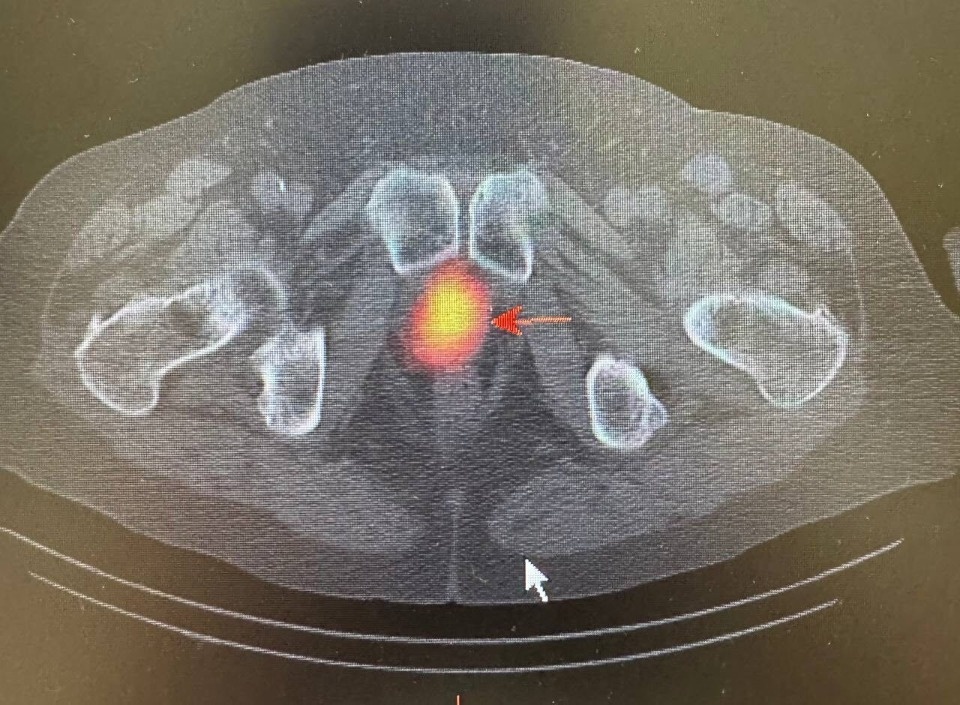

Для получения детальной информации о состоянии лимфатических узлов назначили радионуклидная диагностика. Она позволила определить наличие злокачественного опухолевого процесса в предстательной железе и подтвердить метастатическое поражение ранее выявленных лимфатических узлов к грудной клетке.

Помимо этого, исследование показало активное накопление технеции ПСМА в парааортальных лимфатических узлах с обеих сторон. «При этом, важно отметить, что на компьютерной томографии не было явных структурных изменений, что затрудняло оценку их состояния и возможности метастазирования», – обратили внимание в пресс-службе министерства здравоохранения Псковской области.